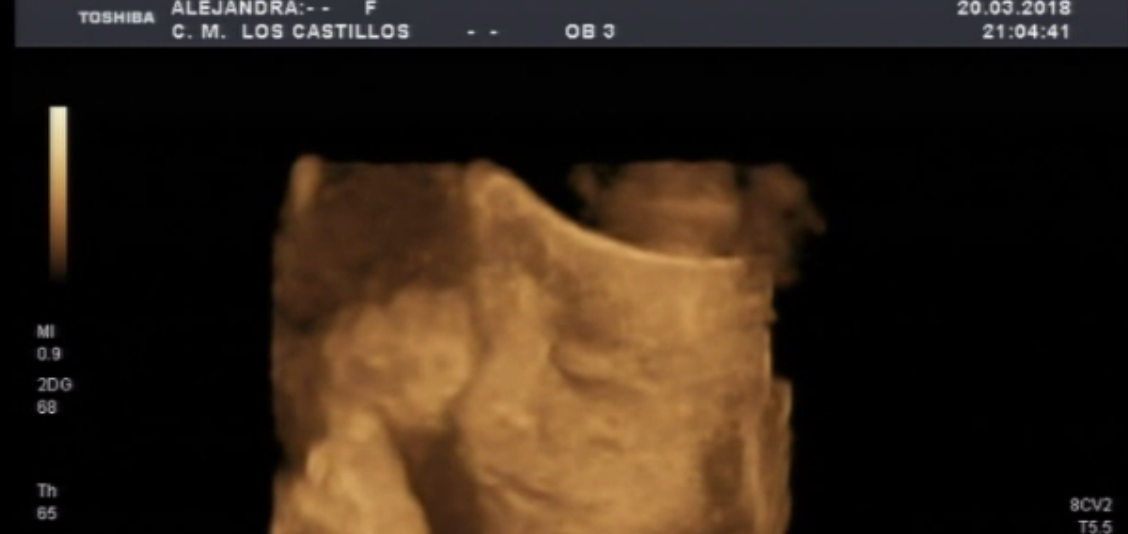

Llaman al teléfono SOS de +Futuro. Son las 11 de la noche, son un grupo de misioneras de extremadura. Acogen y educan a chicas desahuciadas y en riesgo de exclusión social. Una de sus chicas, ya mayor de edad que se ha ido a vivir con la madre de su novio esta de 26 semanas de embarazo. Quieren que aborte todo su entorno. Ella no. Un médico y el abortorio de Badajoz dicen que su niño viene con hidrocefalia. Afirman con contundencia que la madre corre peligro de morirse. (fotos de una ecografía de Alexia, la hija de dos voluntarios de la asociación de 26 semanas).